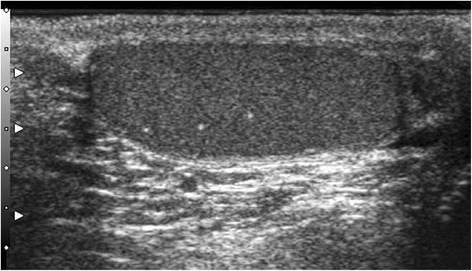

Testicular microlithiasis (TML) corresponds to concretions of hydroxyapatite surrounded by fibrosis located in the seminiferous tubes [1]. They are due to the insufficient capacity of Sertoli cells to phagocyte the degenerate cells present in these tubes. They are commonly discovered by ultrasound (US). They are not visible on Magnetic Resonance Imaging (MRI). In 1987, Doherty et al. [2] described their appearance on US, which is characterized by a hyperechoic focus measuring between 1 and 3 mm in the testicular parenchyma without posterior shadow cone [3] with a number greater than or equal to 5 per testis. The discovery is mostly fortuitous because there is no clinical manifestation. Their historical radiological classification is described by Backus et al. [4]. Three grades are distinguished according to the number of TML described by parenchyma (grade 1: 5 to 10, grade 2: 10 to 20 and grade 3 with more than 20 TML). In recent years, US has substantially improved with the advent of higher resolutions enhancing TML detection. In 2015, the European Society of Urogenital Radiology (ESUR) proposed a summary of guidelines and reported another classification with 3 groups, based on the number of TML per field of vision [5]. These three groups were defined as follows, limited TML: less than 5 per field of view (Fig. 1), classic TML: greater than or equal to 5 per field of view (Fig. 2) and finally diffuse TML, labelled “snowstorm” (Fig. 3). There are many observational studies on TML and testicular cancer risk. The objective was to perform a review of the available literature to date.

Fig. 1.

Limited testicular microlithiasis (TML): less than 5 per field of view. With agreement from authors [8]